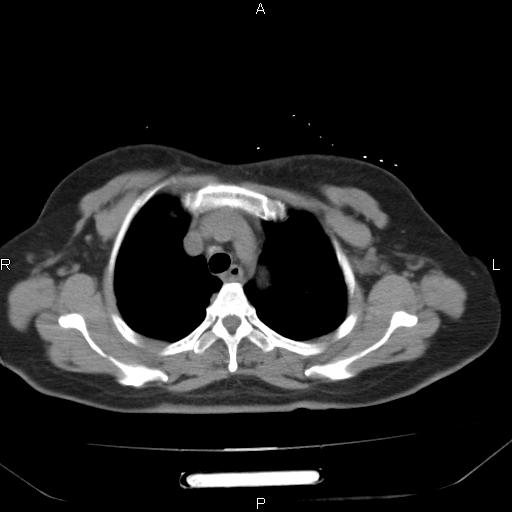

胸腺瘤

女、63Y 双眼睑下垂,早轻晚重。 胸腺瘤???

结果胸腺瘤